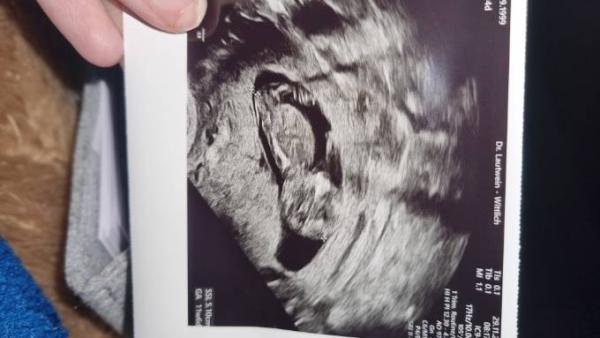

Hallo Mädels, was denkt ihr was es wird ein Mädchen oder vielleicht einen Jungen? Ich bin sehr gespannt und nehme beides sowieso gerne aber freu mich trotzdem auf eure Meinungen!

Hallo ihr Lieben, die kleine Aliyah ist da 🌷🩷